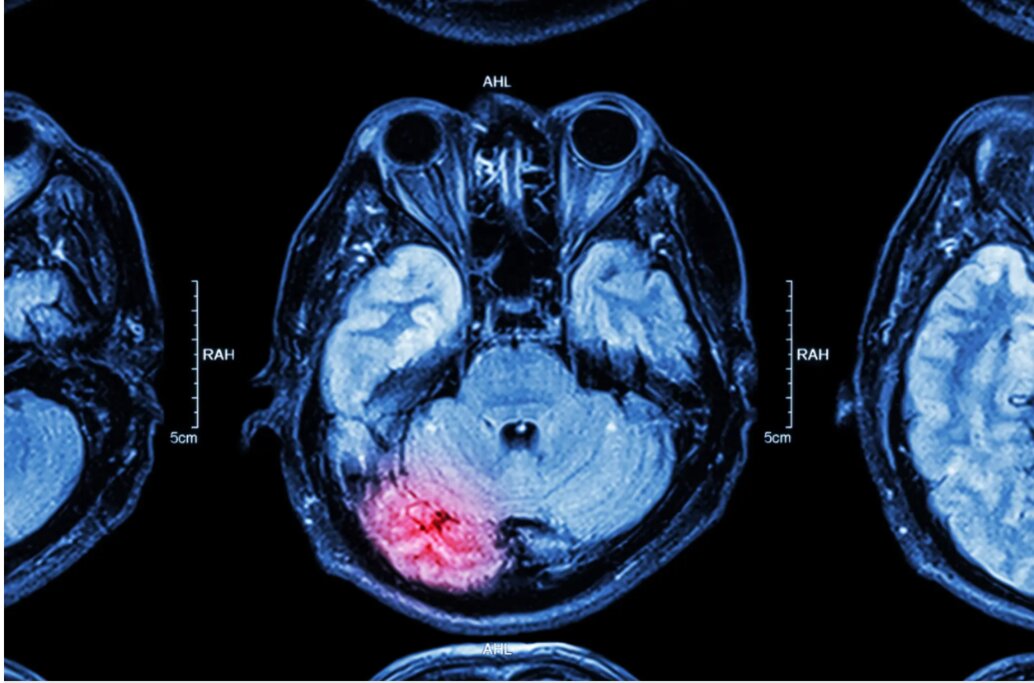

Từng là căn bệnh gắn liền với người cao tuổi, đột quỵ giờ đây đang "tấn công" ngày càng nhiều người trong độ tuổi thanh niên và trung niên.

Theo dữ liệu từ Trung tâm Kiểm soát và Phòng ngừa Dịch bệnh Hoa Kỳ (CDC), số ca đột quỵ ở nhóm tuổi từ 18–44 đã tăng tới 14,6% chỉ trong vòng 2 năm (2020–2022). Điều này đang khiến các chuyên gia y tế đau đầu, đặc biệt khi ngày càng nhiều người trẻ hoàn toàn khỏe mạnh, không có tiền sử bệnh nền, vẫn bị đột quỵ một cách bất ngờ

Tiến sĩ Mohammad Anadani, chuyên gia nội mạch thần kinh tại Viện Khoa học thần kinh Endeavor Health (Mỹ) chia sẻ, gần đây ông đã điều trị cho 2 bệnh nhân trẻ tuổi bị đột quỵ là Ann Fulk (24 tuổi) và Aubrey Hasley (23 tuổi). Cả hai đều không có yếu tố nguy cơ rõ ràng, sức khỏe trước đó được đánh giá là ổn định.

Các xét nghiệm sau đó cho thấy cơn đột quỵ đến từ tình trạng tắc mạch, nghĩa là cục máu đông hình thành ở nơi khác trong cơ thể và trôi lên não. Đáng chú ý, cả hai bệnh nhân đều sử dụng thuốc tránh thai đường uống - một yếu tố được biết là có thể làm tăng nguy cơ hình thành huyết khối.